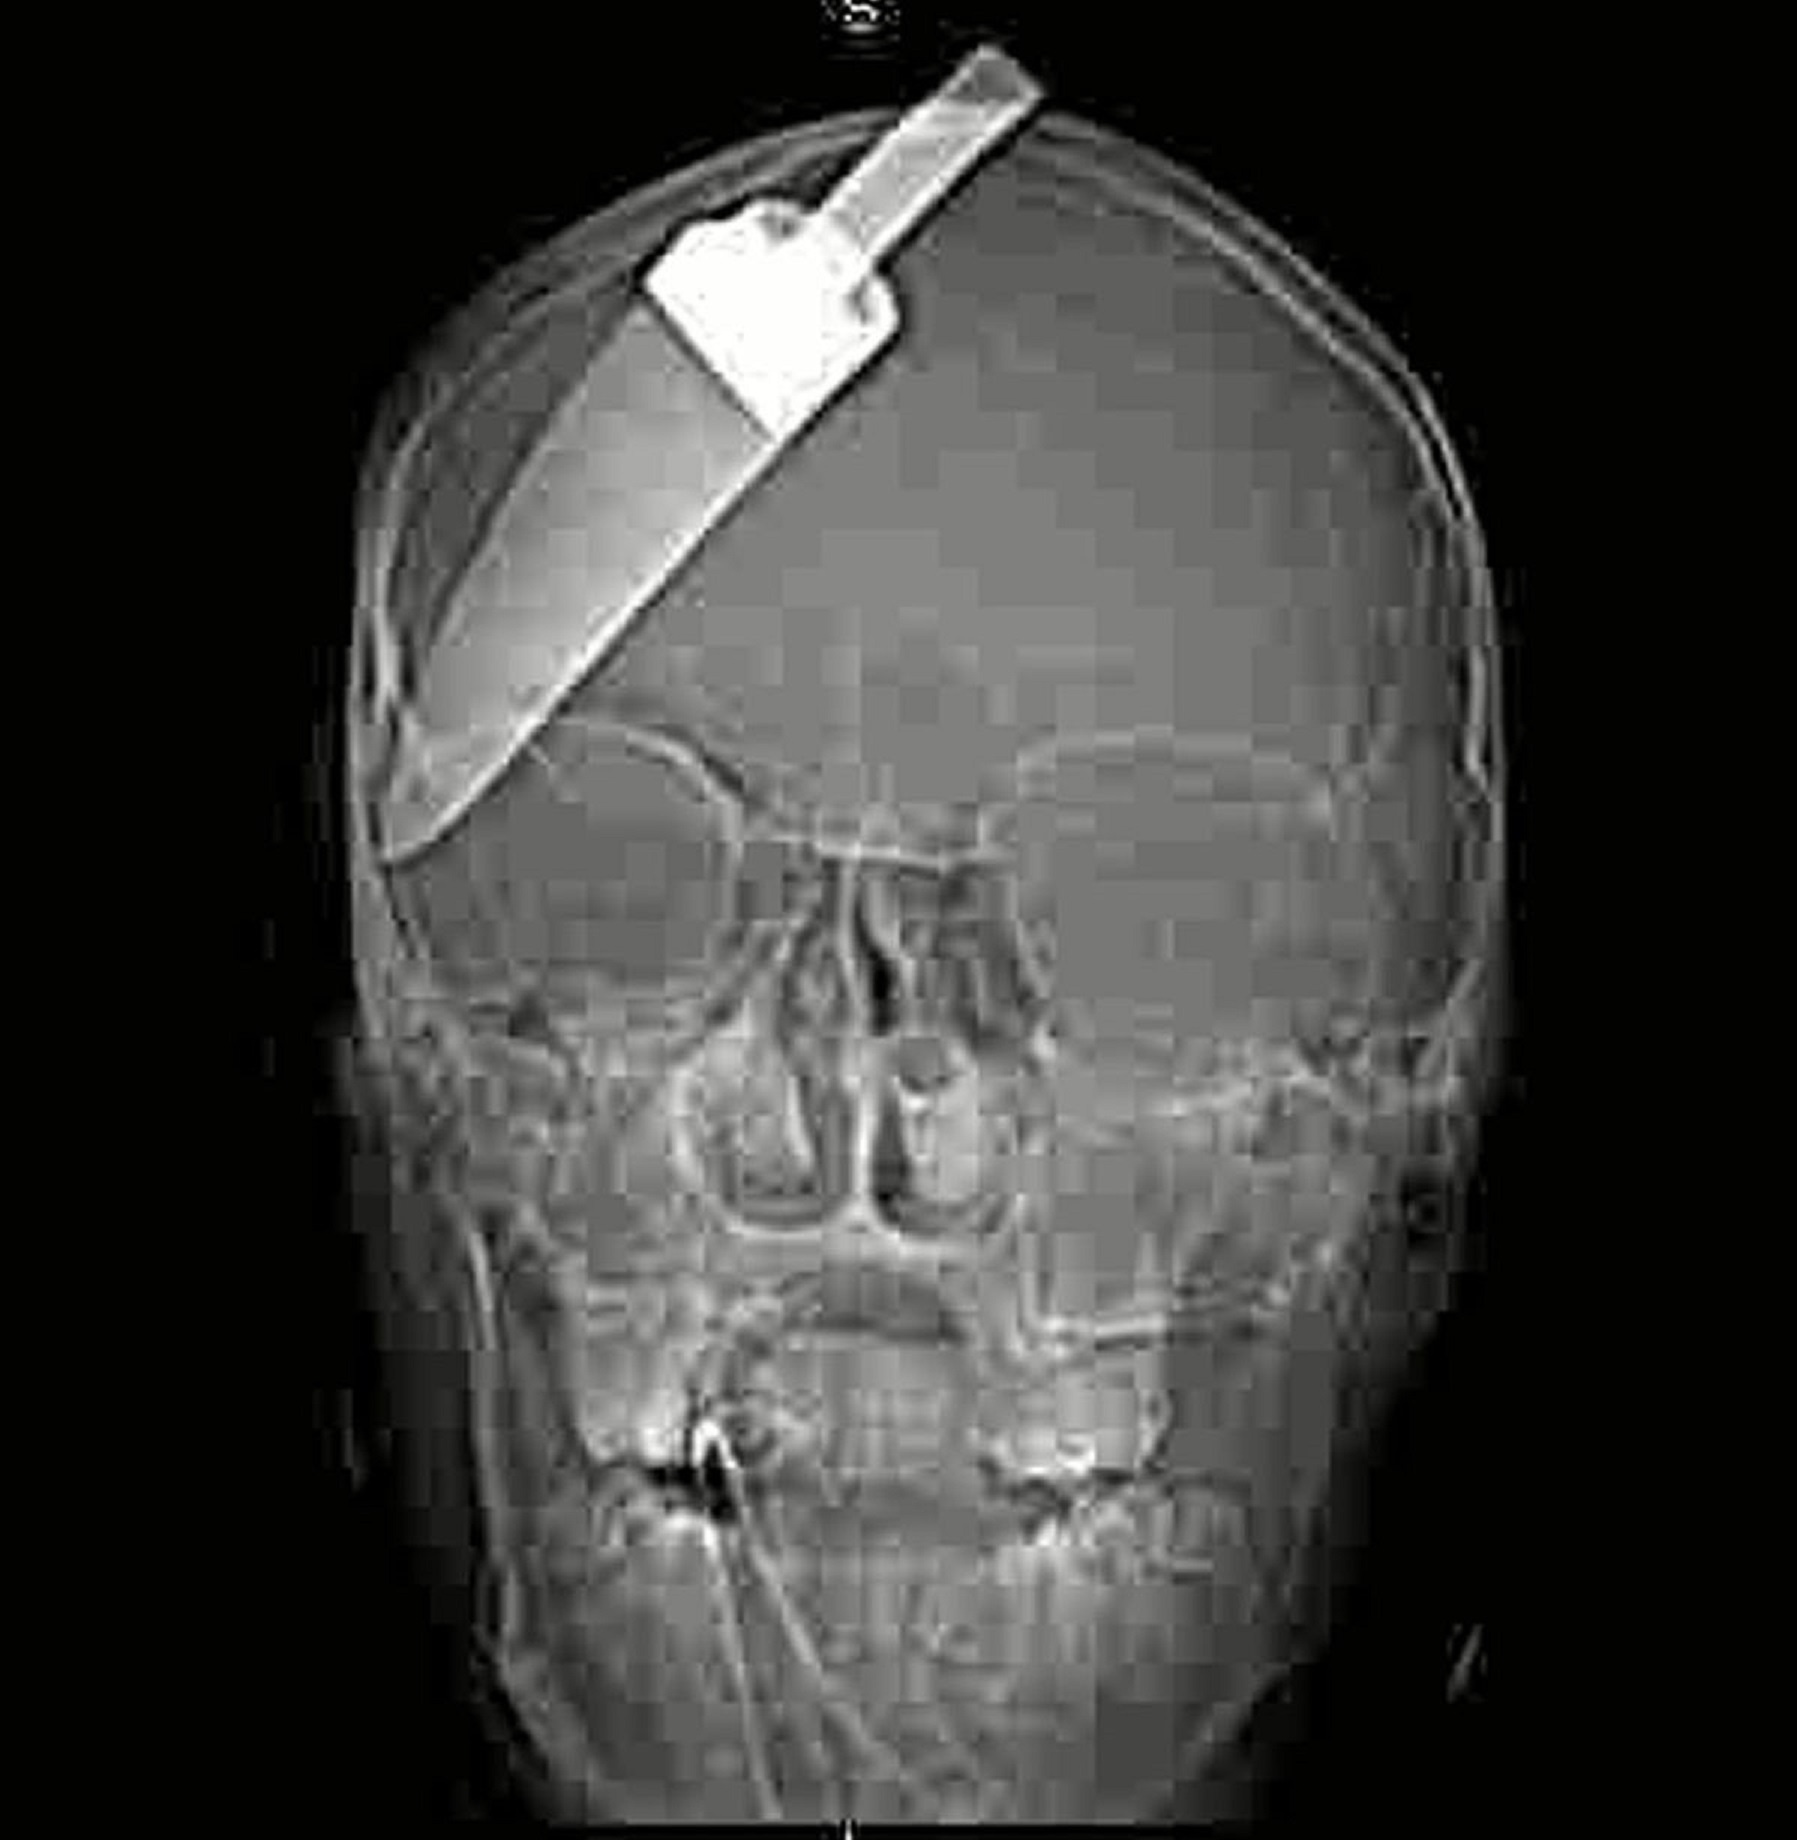

| Con dao có chiều dài gần 13 cm trong sọ một thiếu niên 15 tuổi. |